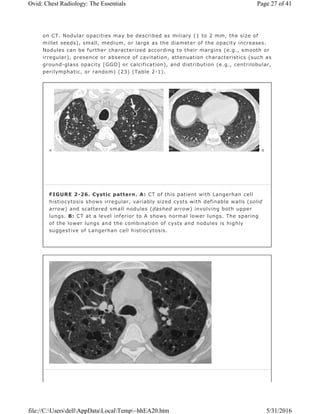

Cystic Pattern

The term “cyst†is nonspecific and refers to a thin-walled (usually less than

3 mm thick), well-defined, well-circumscribed, air- or fluid-containing lesion, 1

cm or more in diameter, that has an epithelial or fibrous wall. A cystic pattern

results from a heterogeneous group of diseases that have in common the

presence of focal, multifocal, or diffuse parenchymal lucencies and lung

destruction (Table 2-1). Pulmonary Langerhan cell histiocytosis,

lymphangioleiomyomatosis, sarcoidosis, lymphocytic interstitial pneumonitis,

collagen vascular diseases, Pneumocystis pneumonia, and honeycombing can

manifest a cystic pattern on CT. Although they do not represent true cystic

disease, centrilobular emphysema and cystic bronchiectasis mimic cystic disease

on chest CT scans.

In cases of Langerhan cell histiocytosis, the cysts are often confluent, usually

thin-walled, and often associated with pulmonary nodules 1 to 5 mm in diameter

that may or may not be cavitary (Fig. 2-26). The intervening lung parenchyma is

typically normal, without evidence of fibrosis or septal thickening. The

distribution of findings is usually upper lungs, with sparing of the costophrenic

sulci. The cysts are distributed diffusely throughout the lungs in

lymphangioleiomyomatosis (Fig. 2-27), and nodules are not a common feature.

FIGURE 2-26. Cystic pattern. A: CT of this patient with Langerhan cell

histiocytosis shows irregular, variably sized cysts with definable walls (solid

arrow) and scattered small nodules (dashed arrow) involving both upper

lungs. B: CT at a level inferior to A shows normal lower lungs. The sparing

of the lower lungs and the combination of cysts and nodules is highly

suggestive of Langerhan cell histiocytosis.